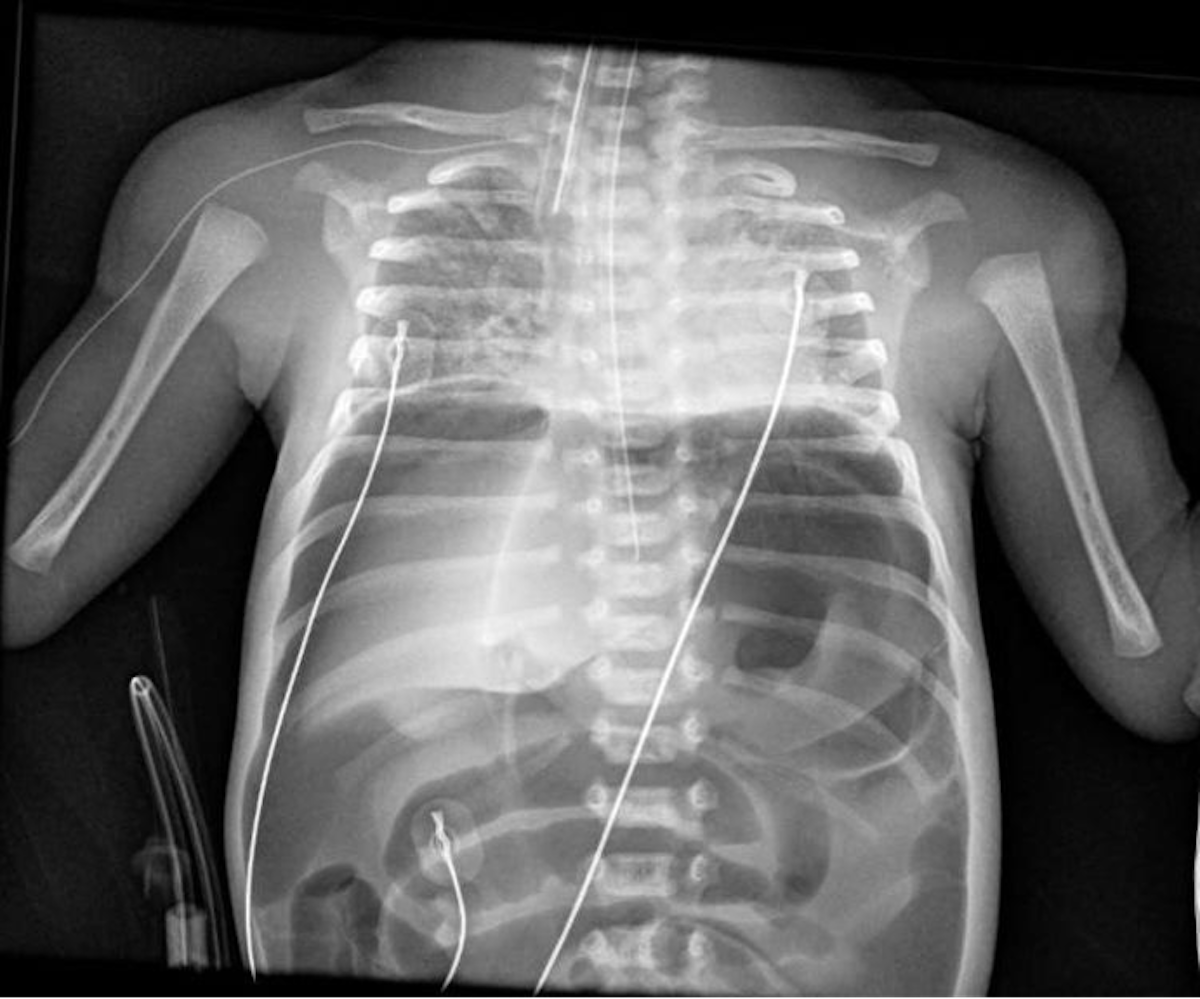

Varón de 32 semanas de gestación, segundo gemelar, de 1850 g, nacido mediante cesárea urgente por amniorrexis prolongada, muerte del primer gemelo, leucocitosis y fiebre materna. Apgar 6/8. Precisa CPAP nasal las primeras horas de vida con buena evolución. A las 36 horas de vida, e iniciada la alimentación enteral, presenta distensión abdominal, apneas, hipoxemia e irritabilidad. Analíticamente destaca hiponatremia y creatinina elevada. Se solicita radiografía de tórax y abdomen (Figura 1).